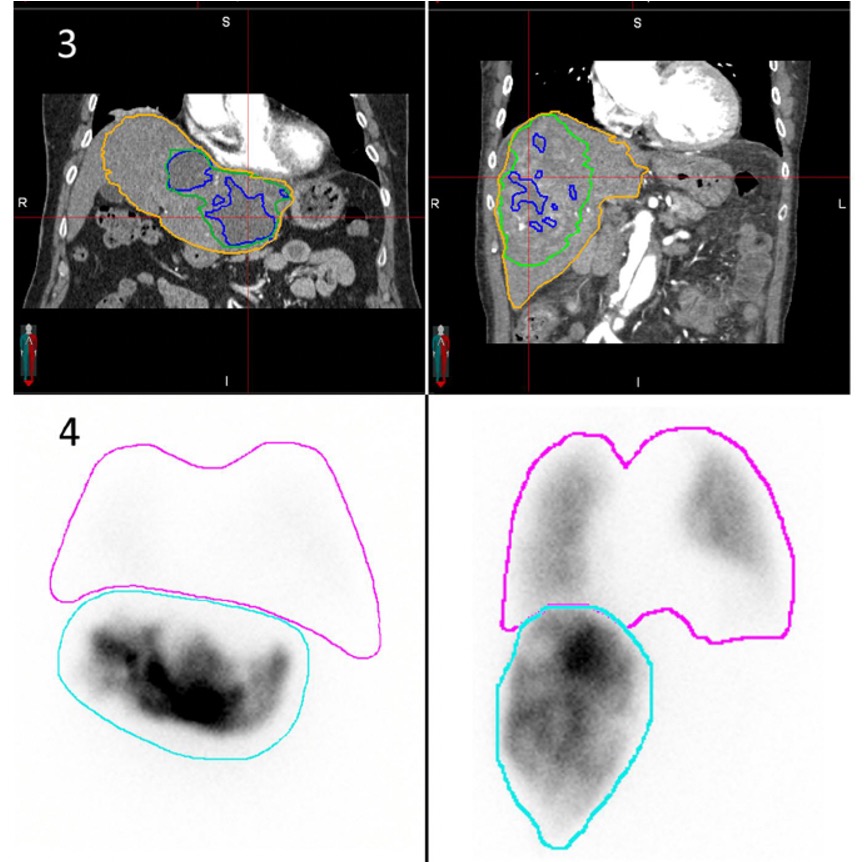

Contrast enhanced CT-derived hypervascular-tumor-to-perfused volume ratio may offer a non-invasive alternative to 99mTc-MAA for lung shunt fraction estimation in hepatic transarterial radioembolization RSNA #RadAdv Oxford Journals Susanna I Lee doi.org/10.1093/radadv…